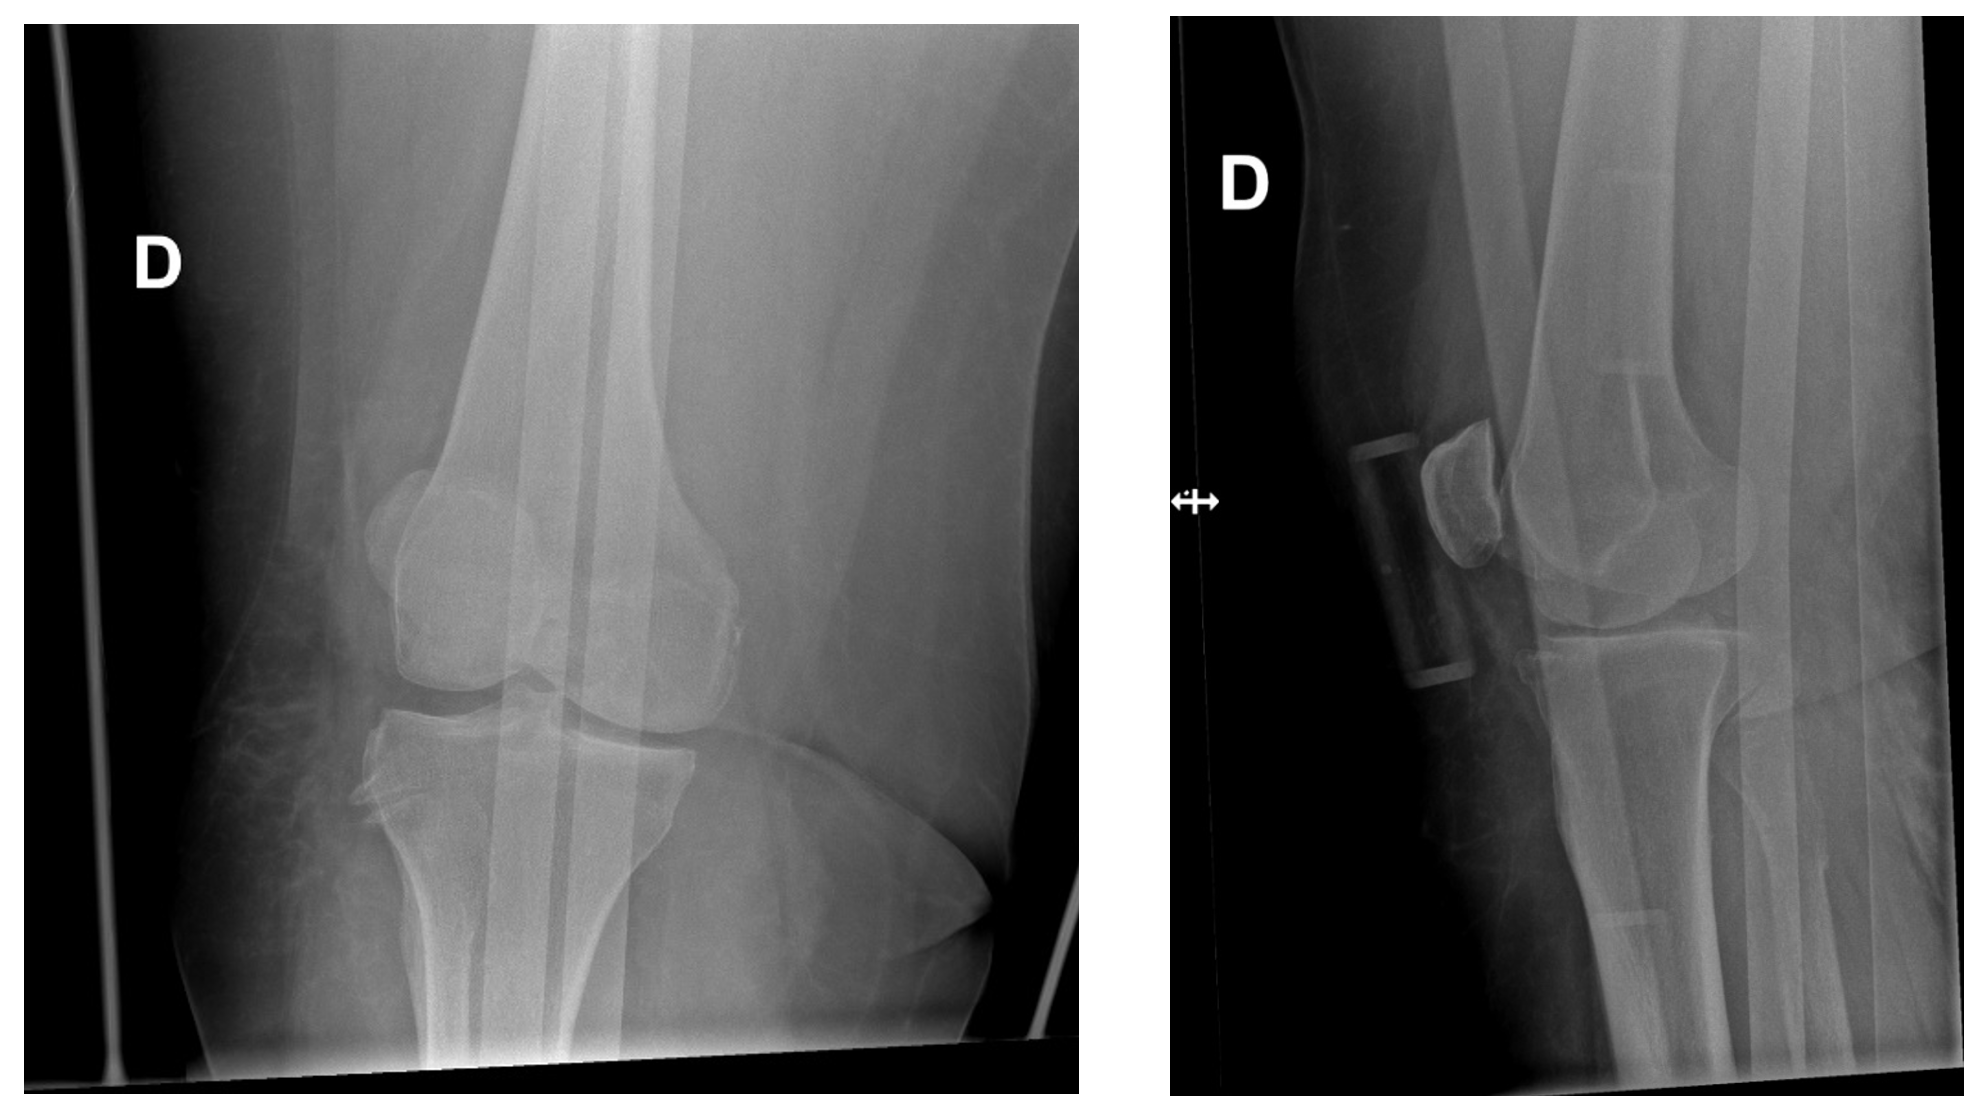

Les radiographies montrent une luxation antérieure du genou avant et après réduction.

Il existe 5 types de luxation, définie par le déplacement du tibia par rapport au fémur : postérieur, antérieur, médial, latéral, et rotatoire. Les luxations antérieures et postérieures sont les plus fréquentes.